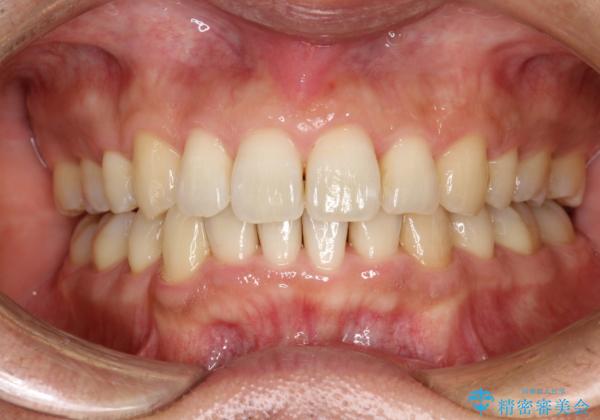

- 以前、上下左右4本抜いてワイヤー矯正をしていた方で、後戻りで下の前歯のガタガタを気にして来院されました。

マウスピース矯正にて、下の歯はIPR(歯と歯の間を削る)を入れることでガタガタの改善、咬み合わせの深さも改善をはかる治療計画をたてました。

歯と歯の間を削って隙間を作って矯正をしています。

保定装置(後戻り防止のための装置)は、基本的にはマウスピースタイプをお渡ししているのですが、患者様のご希望で取り外ししないタイプを希望されたので、前歯の裏側を細いワイヤーで固定(ボンディングリテーナー)を作成しています。